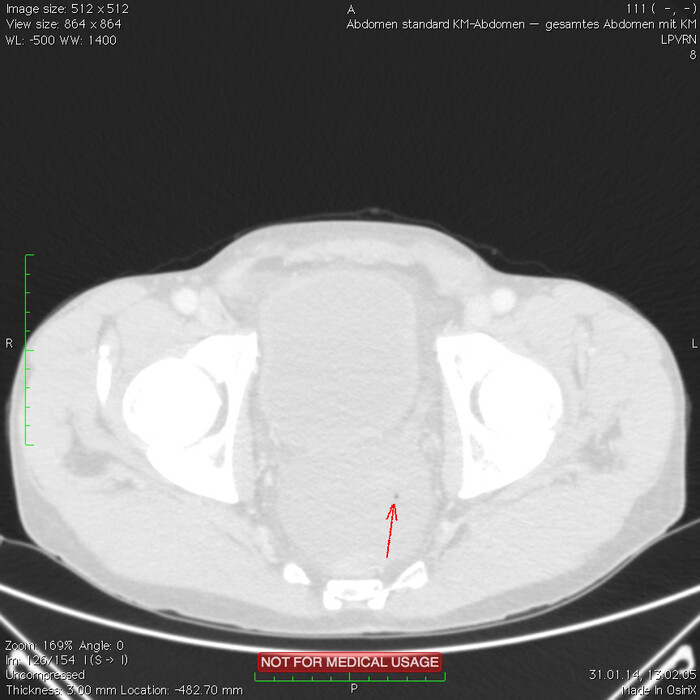

Мужчина, 32 года. Во время игры в футбол получил удар в низ живота, игру продолжил. Впоследствии боли в животе усиливались, стали нестерпимыми, ухудшилось общее самочувствие. На следующий день после игры пошёл сдаваться в больницу. Хирурги клинически описывают разлитой перитонит (воспаление брюшины) и отсылают пациента к нам на КТ, которое мы провели с внутривенной дачей контраста + заставили контраст ещё выпить (специальный раствор для перорального применения).

Так как клиника у нас острого живота после тупой травмы, учитывая что боли во всём животе и признаков большой кровопотери нет, то первое, что ищем - это свободный газ в брюшной полости, и находим его! (для этого лучше всего подходит т.н. лёгочное окно, как представлено ниже, или можно искать в костном окне - это спец.настройки яркости и контраста для просмотра разных структур тела - лёгкие, мозг, мягкие ткани, кости):

Отмечаем про себя, что в верхних квадрантах свободного газа не так уж и много. При перфорации желудка газа намного больше. Также выясняем, что газ есть также и в нижних квадрантах:

Ещё бросается в глаза массивный выпот (стрелки) во всех этажах, а также утолщение брюшины на всём протяжении, что указывает на диффузный (разлитой) перитонит. Тут, кстати, уже мягкотканное окно:

Итак, имеет место быть свободный газ в брюшной полости + свободная жидкость + перитонит. Определённо перфорация! Осталось найти источник. Желудок не подходит по механизму, а точнее по локализации травмы. Мочевой пузырь - в нём нет воздуха. Остаётся методом исключения только кишечник. Толстый или тонкий? Явно не верхние отделы толстого кишечника (ободочная кишка в области печеночного и селезеночного углов, а также поперечная исключаются - было бы больше воздуха). Сигма и нисходящая тоже заполнены стулом и воздухом. Получается, что тонкий кишечник всему виной.

Верхние (проксимальные) отделы точно не причём. Жидкость (звёздочки) больше в малом тазу, тут же и воздух. Для сравнения верхний этаж:

Hижний этаж:

И тут СТОП! А это чтo такое???

Кишке это точно не принадлежит, как ни крути. Это вышедший за пределы кишки контраст, который пациент выпил!

Осталось только место выхода найти:

Итого: перфорация тощей кишки в дистальных отделах, разлитой перитонит.

Был успешно прооперирован, место перфорации ушито, выписан.